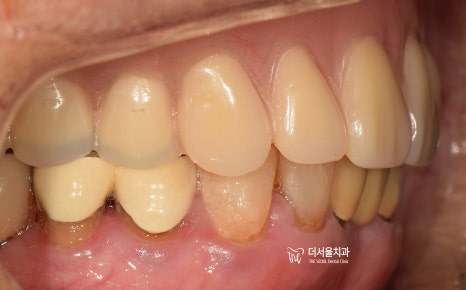

『최종 결과』

이제 여지껏 설명드린 것을

한번에 보여드리면

상, 하악이 전체 수복이 된 것을 볼 수 있습니다.

1) 심미성 재건 완료

2) 구강 내 저작활동 가능